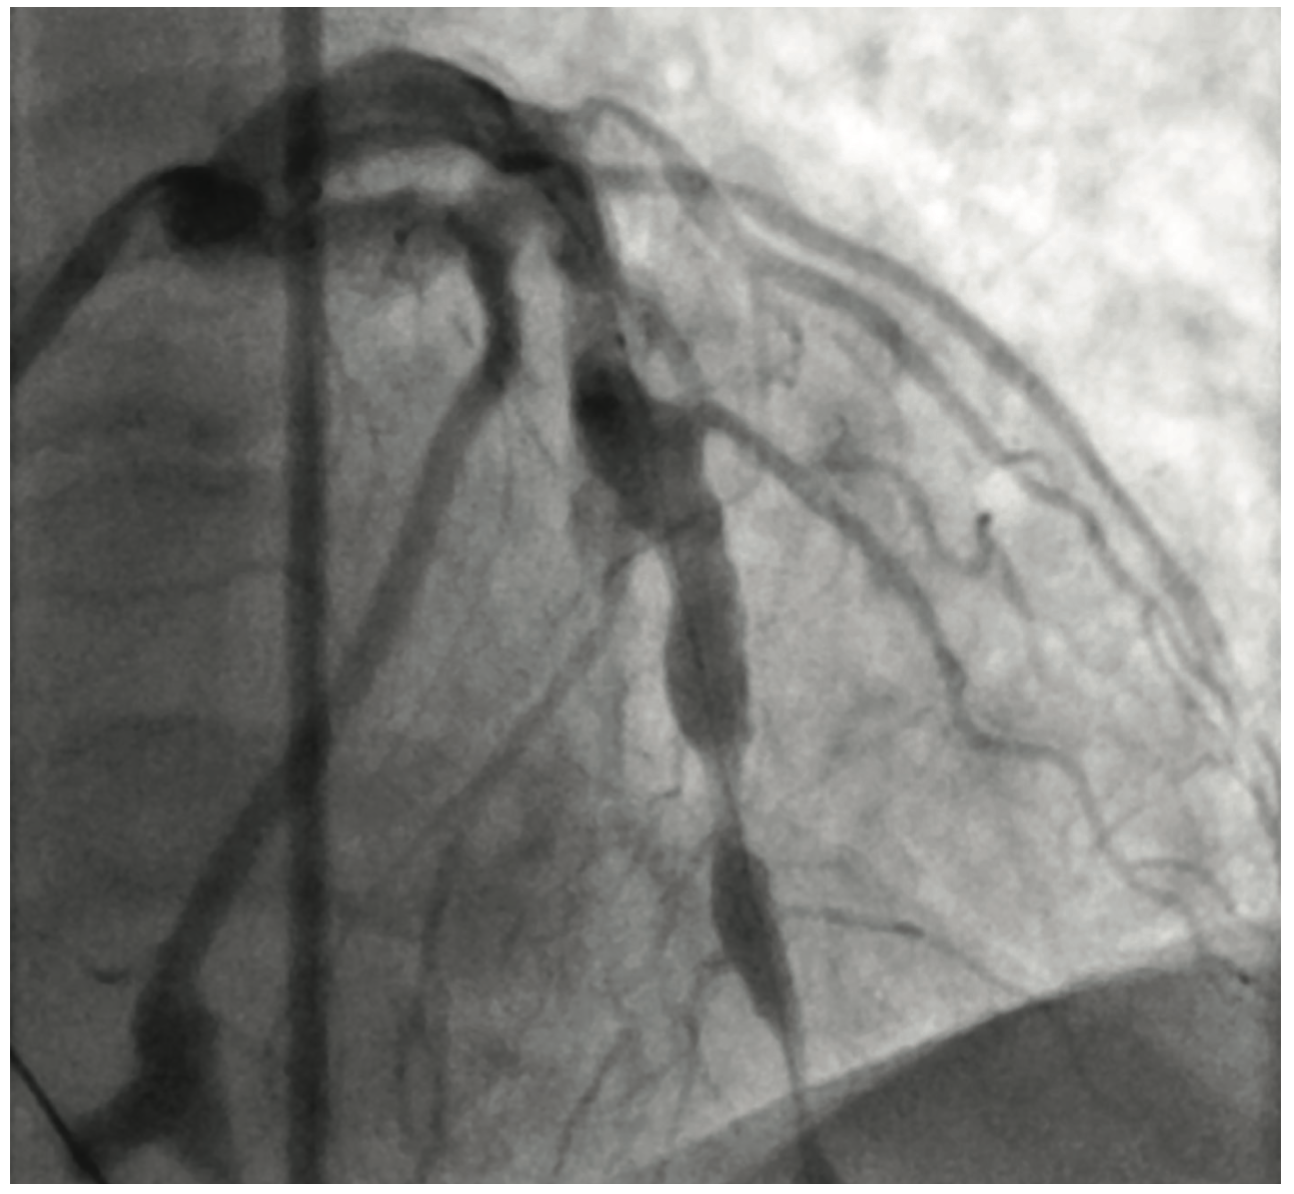

Figure 2. LAD opening after dottering of vessel.

Cardiac catheterization showed total occlusion of the left anterior descending artery (LAD) with multiple coronary aneurysms in the LAD, left circumflex (LCx), and right coronary arteries. There was TIMI 0-1 slow flow within the coronary aneurysms. An eptifibatide bolus and drip was started. Aspiration thrombectomy using an Export catheter (Medtronic) and then rheolytic thrombectomy using an AngioJet catheter was performed on the proximal and mid LAD. A 4.0 x 16 mm bare metal stent was placed. However, the patient became hypotensive in the cath lab and a balloon pump was inserted. Prior to leaving the lab, there was resolution of the ST segment elevations. The patient was started on both a heparin drip and low-dose dopamine drip.